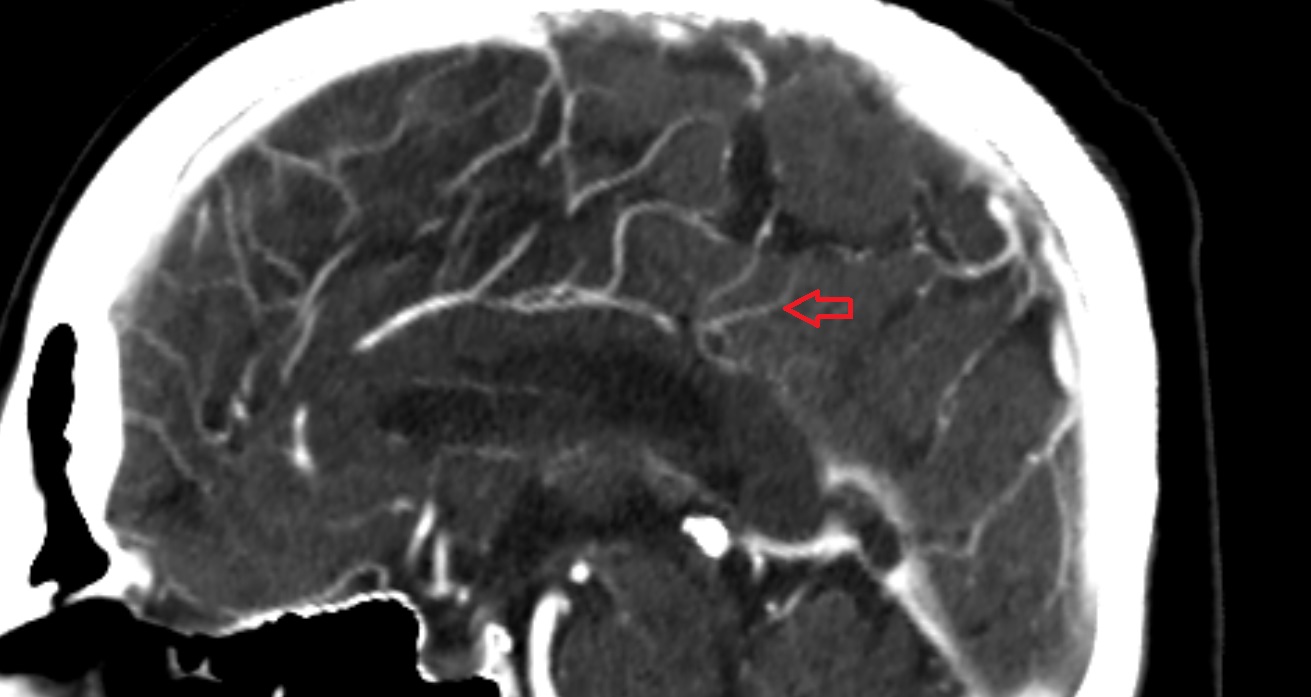

- Middle cerebral artery insular segment (M2)

- Middle cerebral artery opercular segment (M3)

- Middle cerebral artery cortical segment (M4)